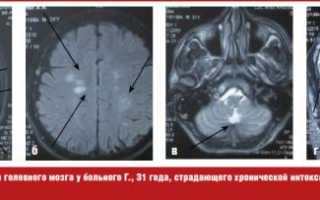

С целью дообследования больному проведена магнитно-резонансная томография (МРТ) головного мозга, на которой выявлены множественные очаги демиелинизации в белом веществе лобных, теменных, височных и левой затылочной долей, субкортикально и паравентрикулярно, в мозолистом теле, ножках мозжечка, в области базальных структур справа размером от 0,3 до 1,0 см без четких контуров, некоторые из них с явлениями перифокального отека (рис. (а, б, в)).

В литературе описаны случаи диффузного повреждения белого вещества у пациентов с дезоморфиновой наркоманией, приводящей к тяжелым расстройствам когнитивных функций, астазией-абазией, экстрапирамидным нарушениям. В данном случае множественное повреждение структур головного мозга в виде рассеянных очагов демиелинизации белого вещества лобных, теменных, височных и затылочной долей, расположенных субкортикально и паравентрикулярно, очагов демиелинизации в мозолистом теле, ножках мозжечка, в области базальных структур, протекающих без какой-либо очаговой пирамидной и экстрипирамидной симптоматики и чувствительных нарушений, возможно, обусловлены систематическим токсическим действием тропикамида, хотя в литературе описаны случаи очаговой демиелинизации вследствие сосудистых, опухолевых и инфекционных поражений [8]. В связи с вышеизложенным для окончательного установления причины морфологических изменений головного мозга в данном случае целесообразно проведение прижизненной биопсии головного мозга, от которой пациент отказался. Магнитно-резонансная томография с контрастным усилением, рекомендованная пациенту через 6 месяцев, проведена не была в связи с развитием у пациента в указанные сроки острого психоза и госпитализацией его в психиатрическое отделение.